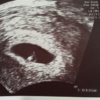

Jest wszystko ok niewiadomo skad wczoraj to krwawienie ale dzisiaj macica czyściutka bez żadnej krwi mam sie oszczędzać odpoczywać zmniejszyła mi progesteron z 6 na 3 dziennie Utrogest i dalej 1x Prolutex dziennie

Zarodek było widac na zdj dzisiaj ewidentnie lepszy sprzet niz w szpitalu wczoraj. I nawet seruszko pukało malusie takze do następnej wizyty choc troche spokoju Zobacz załącznik 739729